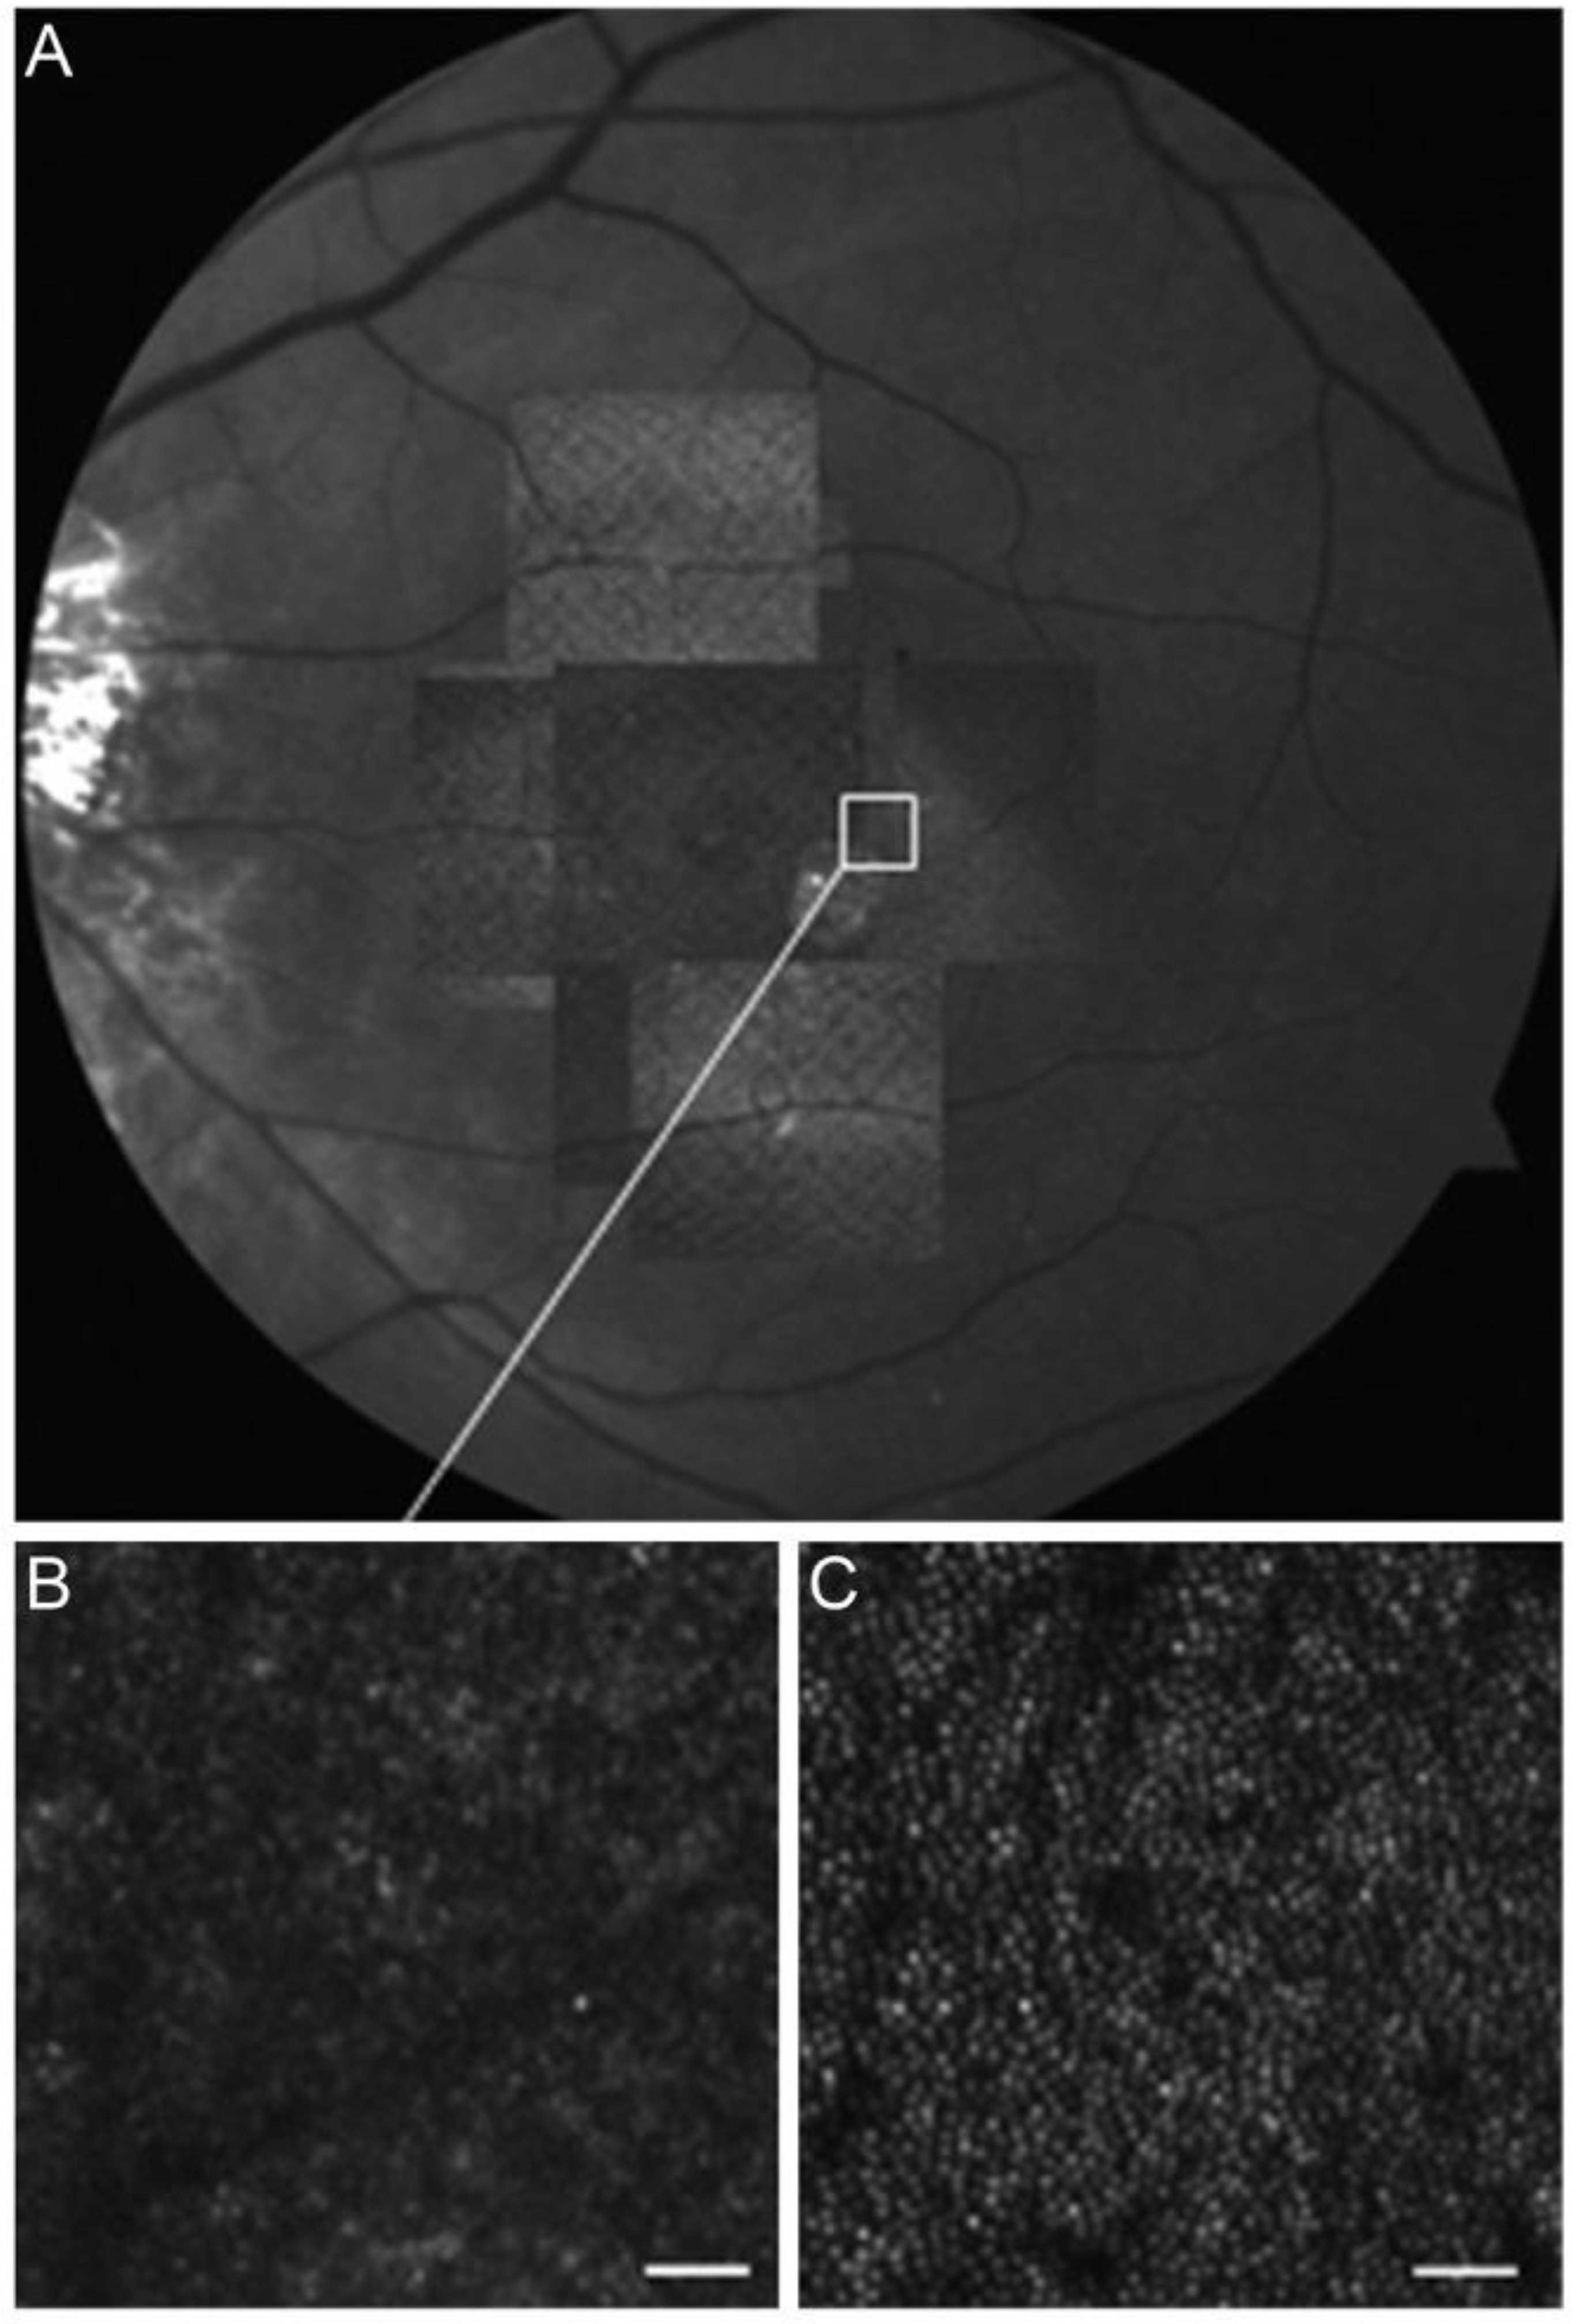

- Godara, P.; Dubis, A.M.; Roorda, A.; Duncan, J.L.; Carroll, J. Adaptive Optics Retinal Imaging: Emerging Clinical Applications. Optom. Vis. Sci. 2010, 87, 930–941. [Google Scholar] [CrossRef]

- Akyol, E.; Hagag, A.M.; Sivaprasad, S.; Lotery, A.J. Adaptive Optics: Principles and Applications in Ophthalmology. Eye 2021, 35, 244–264. [Google Scholar] [CrossRef]

- Lombardo, M.; Serrao, S.; Devaney, N.; Parravano, M.; Lombardo, G. Adaptive Optics Technology for High-Resolution Retinal Imaging. Sensors 2012, 13, 334–366. [Google Scholar] [CrossRef]

- Bae, E.J.; Kim, K.R.; Tsang, S.H.; Park, S.P.; Chang, S. Retinal damage in chloroquine maculopathy, revealed by high resolution imaging: A case report utilizing adaptive optics scanning laser ophthalmoscopy. Korean J. Ophthalmol. 2014, 28, 100–107. [Google Scholar] [CrossRef] [PubMed]

- Debellemanière, G.; Flores, M.; Tumahai, P.; Meillat, M.; Bidaut Garnier, M.; Delbosc, B.; Saleh, M. Assessment of Parafoveal Cone Density in Patients Taking Hydroxychloroquine in the Absence of Clinically Documented Retinal Toxicity. Acta Ophthalmol. 2015, 93, e534–e540. [Google Scholar] [CrossRef] [PubMed]

- Babeau, F.; Busetto, T.; Hamel, C.; Villain, M.; Daien, V. Adaptive Optics: A Tool for Screening Hydroxychloroquine-Induced Maculopathy? Acta Ophthalmol. 2017, 95, e424–e425. [Google Scholar] [CrossRef] [PubMed]

- Ueda-Consolvo, T.; Oiwake, T.; Abe, S.; Nakamura, T.; Numata, A.; Hayashi, A. Hydroxychloroquine’s Early Impact on Cone Density. J. Ophthalmol. 2021, 2021, 1389805. [Google Scholar] [CrossRef] [PubMed]